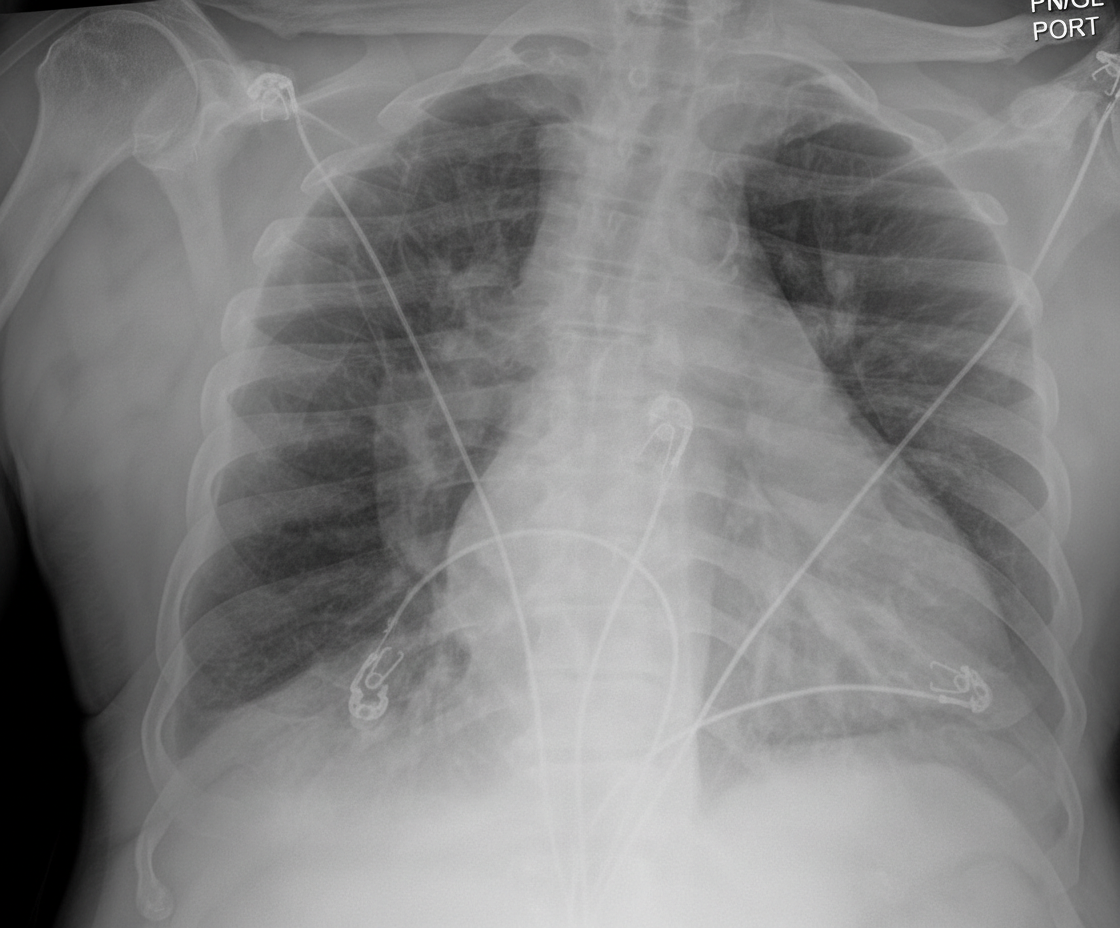

A 25-year-old male graduate student is brought to the emergency department for respiratory distress after he was found by his roommate coughing and severely short of breath. He was diagnosed with HIV infection 3 months ago but is not compliant with his antiretroviral therapy. He is from Chile and moved here 5 years ago. He appears unwell and is unable to speak in full sentences. His temperature is 38.2°C (100.7°F), pulse is 127/min, respirations are 32/min, and blood pressure is 95/65 mm Hg. Pulse oximetry shows an oxygen saturation of 86% on room air. No oral thrush is seen. The patient is placed on supplemental oxygen. Serum studies show: Lactate dehydrogenase 364 IU/L CD4 cell count 98/mm3 Beta-D-glucan elevated Arterial blood gas analysis shows: pH 7.50 PaCO2 22 mm Hg PaO2 60 mm Hg HCO3 20 mEq/L An x-ray of the chest is shown. Standard antibiotic therapy is begun immediately. The most appropriate next step in management is administration of which of the following?